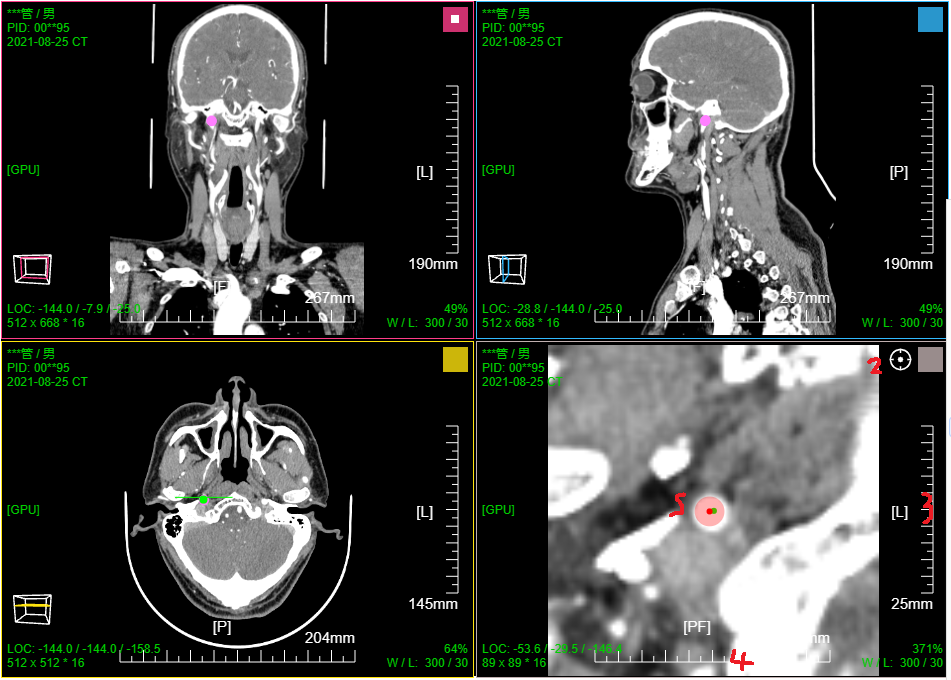

七、PET CT / MR融合功能操作和截图

二维融合,三视图显示;滚动滚轮三个序列窗口联动;

三维融合; 支持 MPR 9窗口视图;MPR+MIP 12窗口视图; (AXIS或CORO或SAGI)切片+MIP 6窗口视图

PT序列MIP窗口滚轮默认水平旋转; 其它序列MIP窗口滚轮默认缩放

PT序列MIP窗口左键默认缩放; 融合序列MIP窗口左键默认移动; CT序列MIP窗口左键默认旋转

点击MPR窗口右上角颜色块可AXIS轴位、CORO冠位、SAGI矢位切片切换

鼠标右键点击MPR窗口左下 切片位置指示器 可显隐十字交叉线; 左键点击MPR复位

鼠标左键点击MIP窗口左下 三维旋转状态指示器 可快速旋转到指定面; 右键点击三维旋转复位

PT序列MIP窗口拖动 "绿色X" 自动计算并定位最大SUV点位置并定位十字交叉线刷新显示MPR